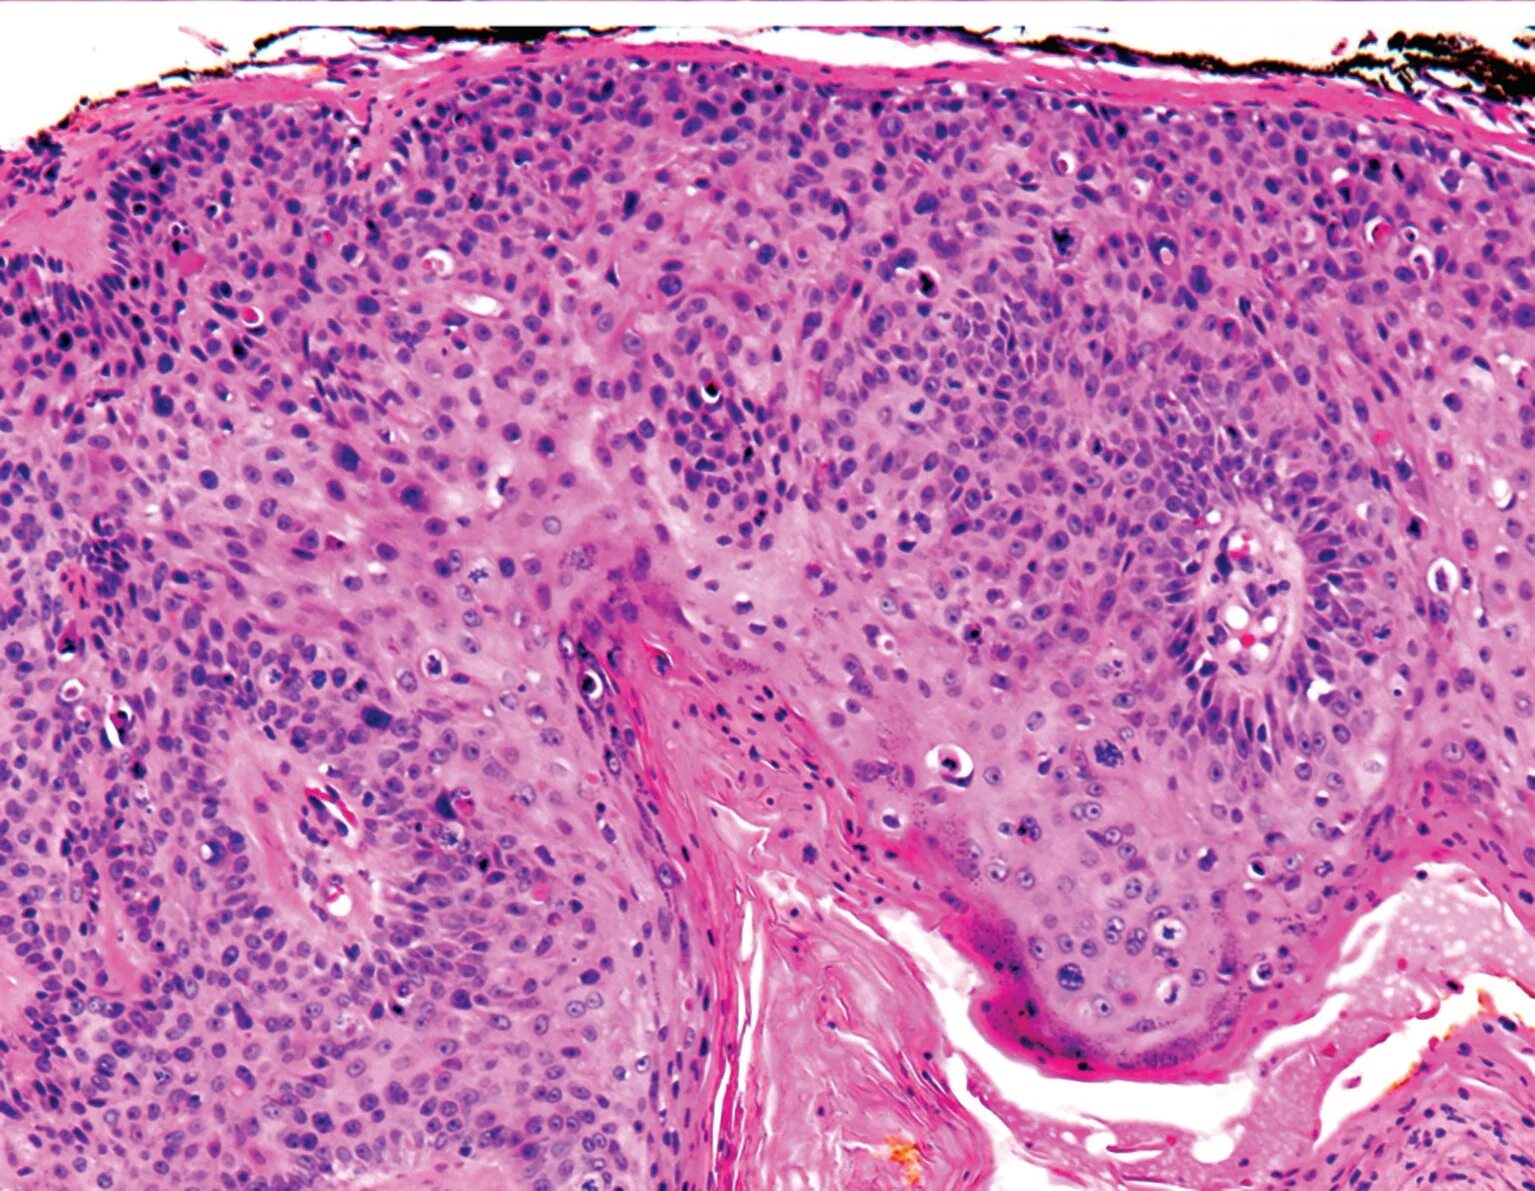

Сухая ороговевающая кожа